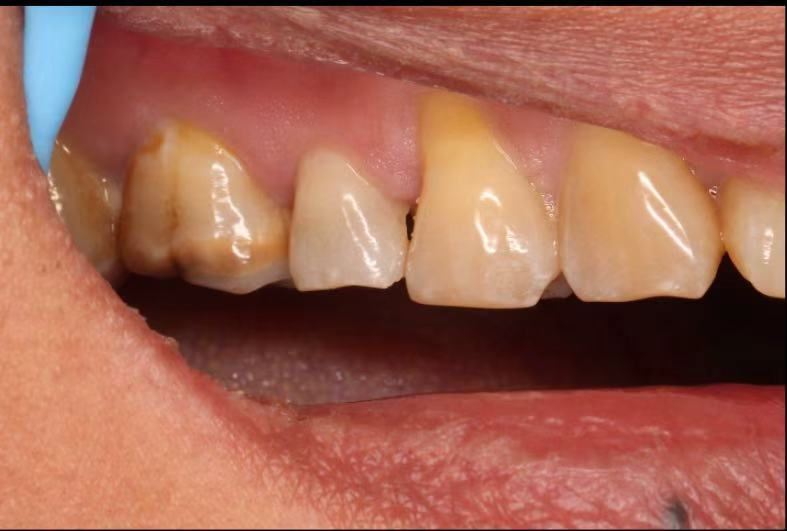

June 20, 2025: The patient's chief complaint is that endodontic treatment was performed on the right maxillary posterior tooth abroad, and a deep carious lesion has been recently detected, requiring restoration. The following are the intraoral photographs taken upon the patient's first visit: a large carious lesion is visible on the occlusal surface of tooth 15 (FDI numbering), with only the buccal wall remaining. Percussion test and cold-hot stimulation test showed no response, and yellow obturation material is visible at the root canal orifices.